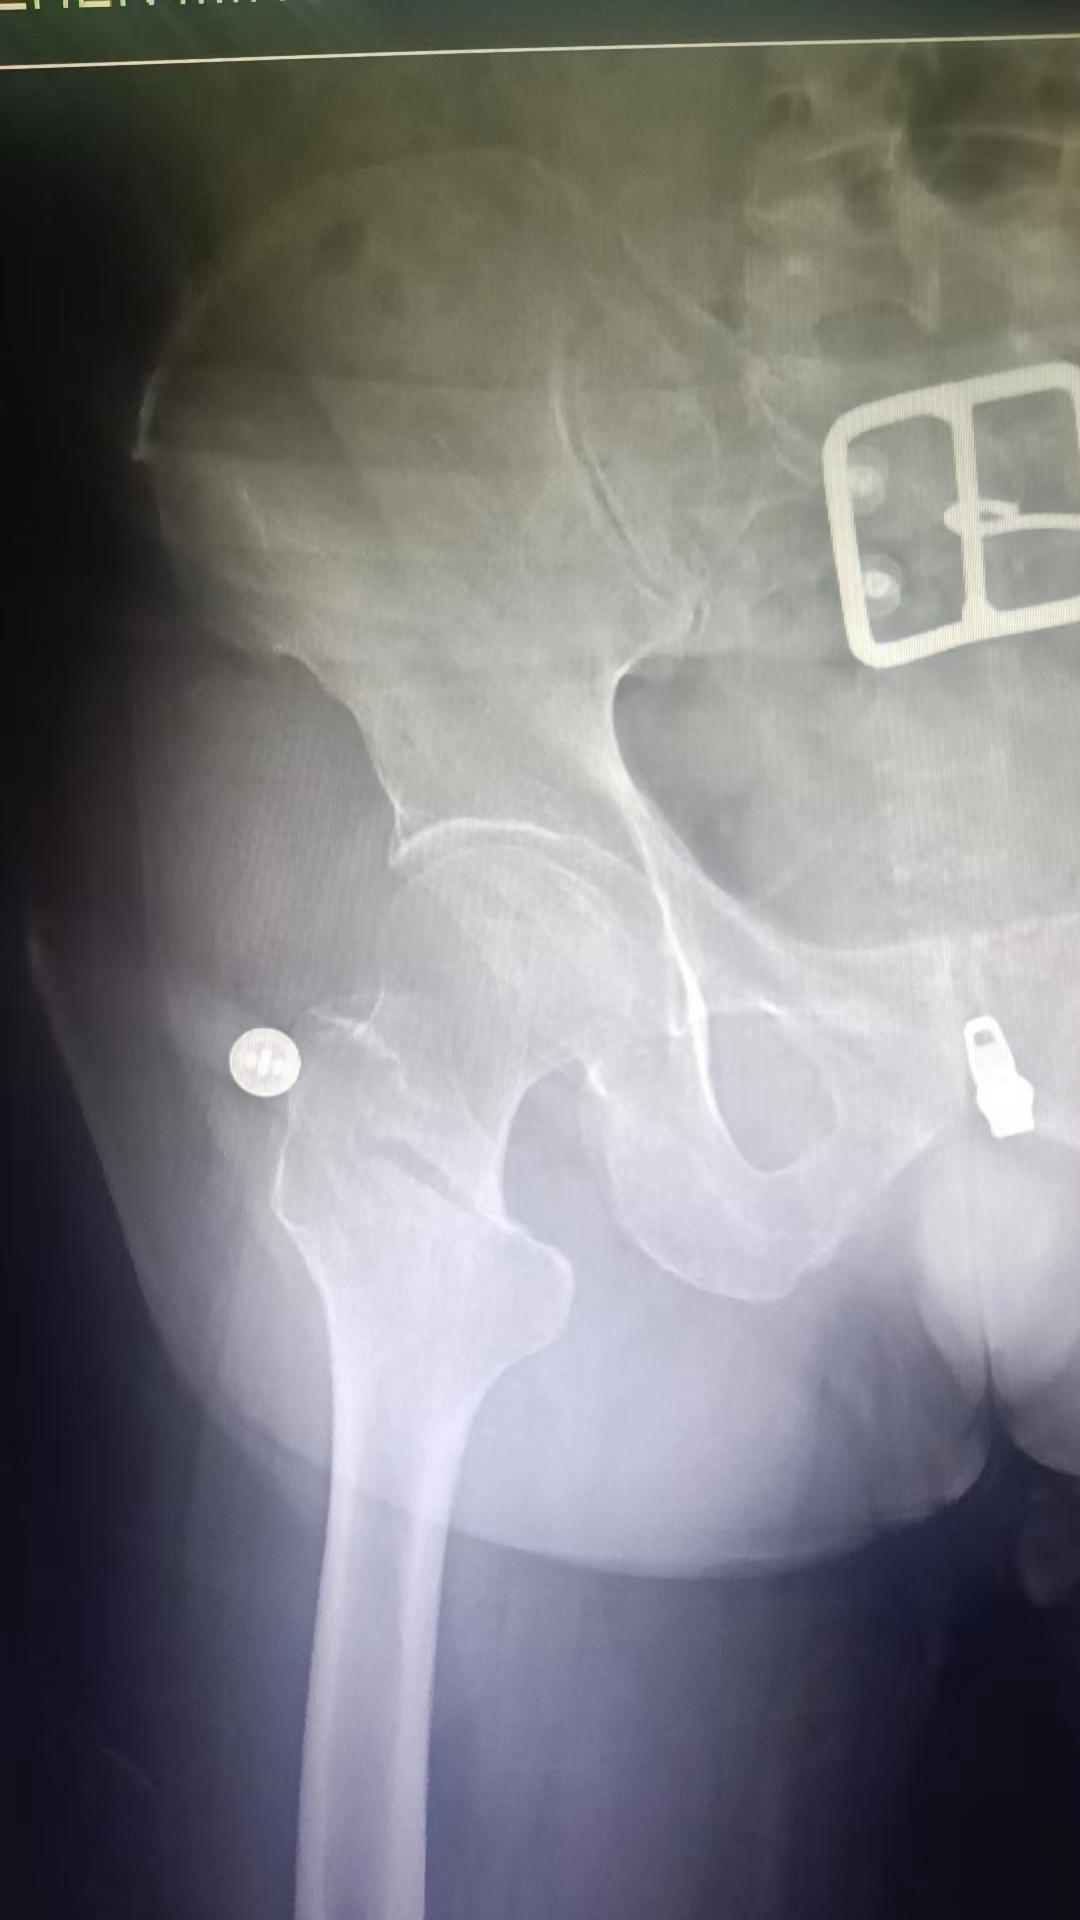

股骨颈骨折。老年体弱股骨颈骨折患者,人工股骨头置换可以使其立即下床,但对于脑梗塞后遗症,肌力小于3级的病人并不适合,所以这例患者使用了PFN。为病人选择最合适的、最受益的手术方式是外科医生的追求🌹